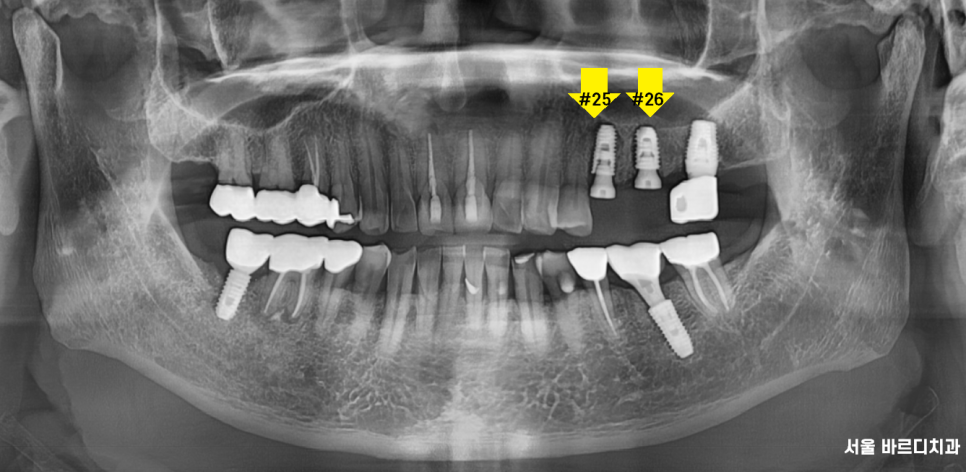

23.07.06

전반적으로 잇몸이 조금씩 내려간 부분은 있었지만

제일 문제가 되는 부분은 왼쪽 위였습니다.

파노라마 전체 사진상으로도

좋아 보이지 않아

자세히 관찰할 수 있는

작은 x-ray를 한 장 더 찍어 보았습니다.

노랗게 동그라미 친 부분이

치아 뿌리 끝에 염증을 의미합니다.

이미 치료를 받은 치아에 염증이 생겨

주변 뼈를 녹이고 있는 상태

옆에 치아도 좋지 않은 것은 마찬가지였습니다.

23.07.11

수술 당일 발치를 진행하고

x-ray를 찍었습니다.

남아있는 치아 뿌리는 없는지?

눈으로 1차 확인하였지만

한 번 더 안전한 과정을 거친 후 수술을 진행

발치 후 당일 임플란트 식립 후 사진입니다.